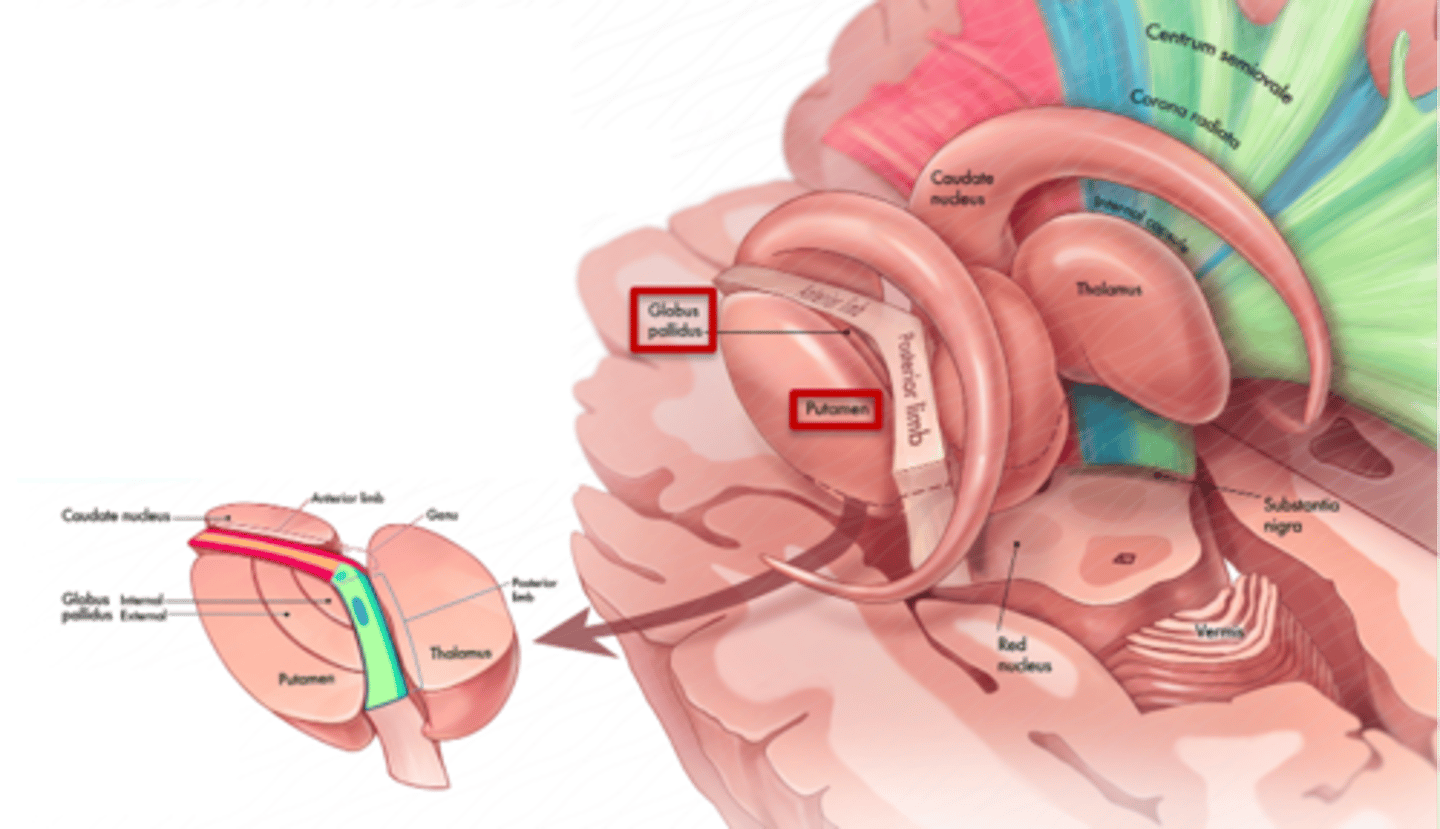

what are 3 key white matter structures found in the cerebrum?

1. corpus callosum

2. corona radiata

3. internal capsule

what cerebral white matter structure is a large bundle of nerve fibers that connects the left and right cerebral hemispheres, allowing them to communicate?

corpus callosum

what is the fan-shaped cerebral white matter sheet that is continuous ventrally with the internal capsule?

corona radiata

what cerebral white matter structure is a tract that carries sensory and motor information to and from the cerebral cortex?

internal capsule

what cerebral white matter structure is found between the basal ganglia?

internal capsule

what are the 3 regions of the internal capsule?

1. anterior limb

2. genu

3. posterior limb

what cerebral gray matter structure is a collection of subcortical nuclei primarily involved in motor control?

basal ganglia

what cerebral gray matter structure has a gate-keeping mechanism for the initiation of motor movement (choosing which actions to allow and which to inhibit)?

basal ganglia

what cerebral gray matter structure has roles in motor learning, executive functions, behaviors, and emotions?

basal ganglia

what are the 3 parts of the basal ganglia? what runs between them?

1. caudate nucleus

2. putamen

3. globus pallidus

internal capsule

what part of the basal ganglia is the C-shaped structure that is most medial?

caudate nucleus

what part of the basal ganglia is medial to the putamen?

globus pallidus

the putamen and globus pallidus of the basal ganglia are collectively called the _______________ nucleus

lentiform